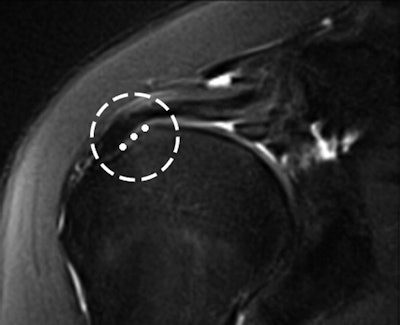

The rotator cable was visualized in 74% of the MRI studies on both coronal and sagittal oblique sequences by both readers. The mean width of the cable was 1.24 ± 0.31 cm and the mean thickness was 0.19 ± 0.05 cm.